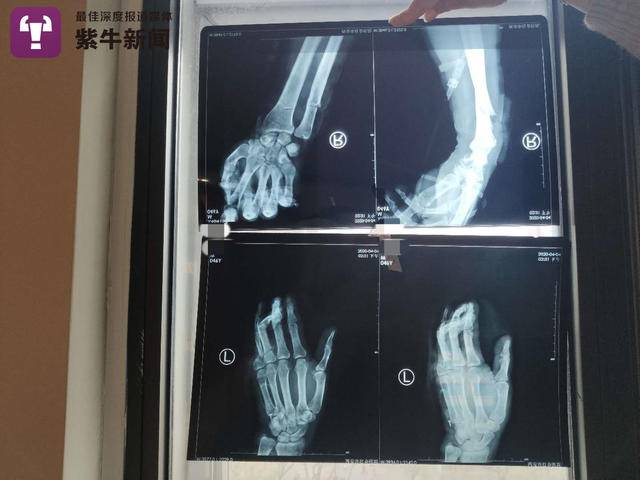

案件发生后,小区物业的工作人员拨打了120,并跟随急救车前往西安市红会医院,付师傅入院后共抢救了22个小时,他的妻子和女儿得知消息也迅速赶往医院。紫牛新闻记者看见付师傅的诊断书上写道,其“被人用刀砍伤致头部、左肩部、胸腹部、双手疼痛、出血。。。。。。出现失血性休克,左侧第7肋骨骨折,头部损伤、头皮裂伤腹部开放性损伤,右尺桡骨开放骨折,告病危。”

4月7日,付师傅的女儿告诉紫牛新闻记者,目前付师傅仍在ICU接受救护,医生表示生命体征正常,可以跟人进行沟通交流,没有肾脏损伤,但一次性失血过多已经对机体造成不可逆的伤害。左肩到左胸肌肉被砍断,右手筋腱全部断掉。左手手指接住现只求保活。事发后,伤人者张某被西安市灞桥公安分局刑事拘留,但令付师傅家人气愤的是,张某的家属并未就此事向付师傅表示歉意。“据当时在现场的目击者说,张某的妻子全程在旁边,看见我的爸爸被捅,完全没有上前阻拦,直到现在,我们也没有收到一句来自他们家人的道歉,甚至完全没有联系过我们。”